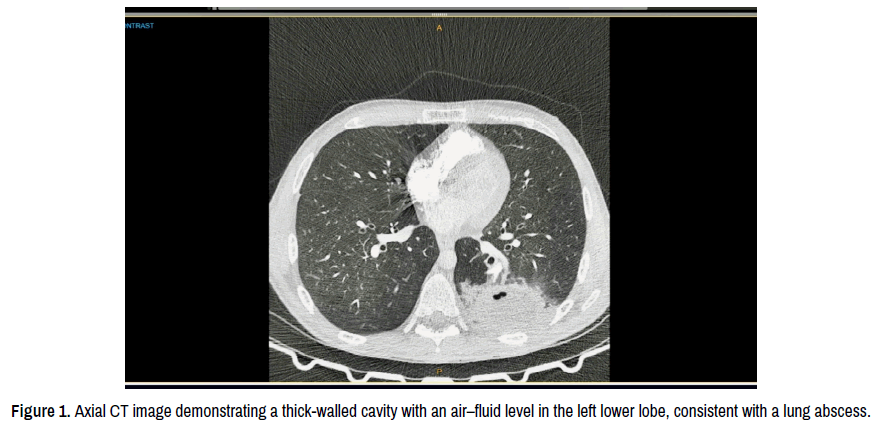

Laboratory investigations demonstrated a white cell count of 11.8 × 10⁹/L with neutrophilia, a C-reactive protein of 63 mg/L, a haemoglobin of 100 g/L, hypoalbuminaemia at 32 g/L and mild derangement of liver enzymes. Blood cultures remained negative. Imaging with computed tomography pulmonary angiogram ruled out pulmonary embolism but showed left lower-lobe consolidation with gas lucencies (Figure 1). A subsequent CT chest confirmed a thick-walled cavitary lesion measuring 58 × 58 × 36 mm with an air-fluid level. Thoracic ultrasound confirmed a loculated fluid-gas collection without pleural effusion. Sputum culture revealed mixed oral flora including anaerobes. A follow-up CT after one week demonstrated a stable cavity with no interval enlargement or pleural involvement (Figure 2).

Figure 2. Follow-up axial CT image showing a stable cavity with resolving surrounding consolidation.